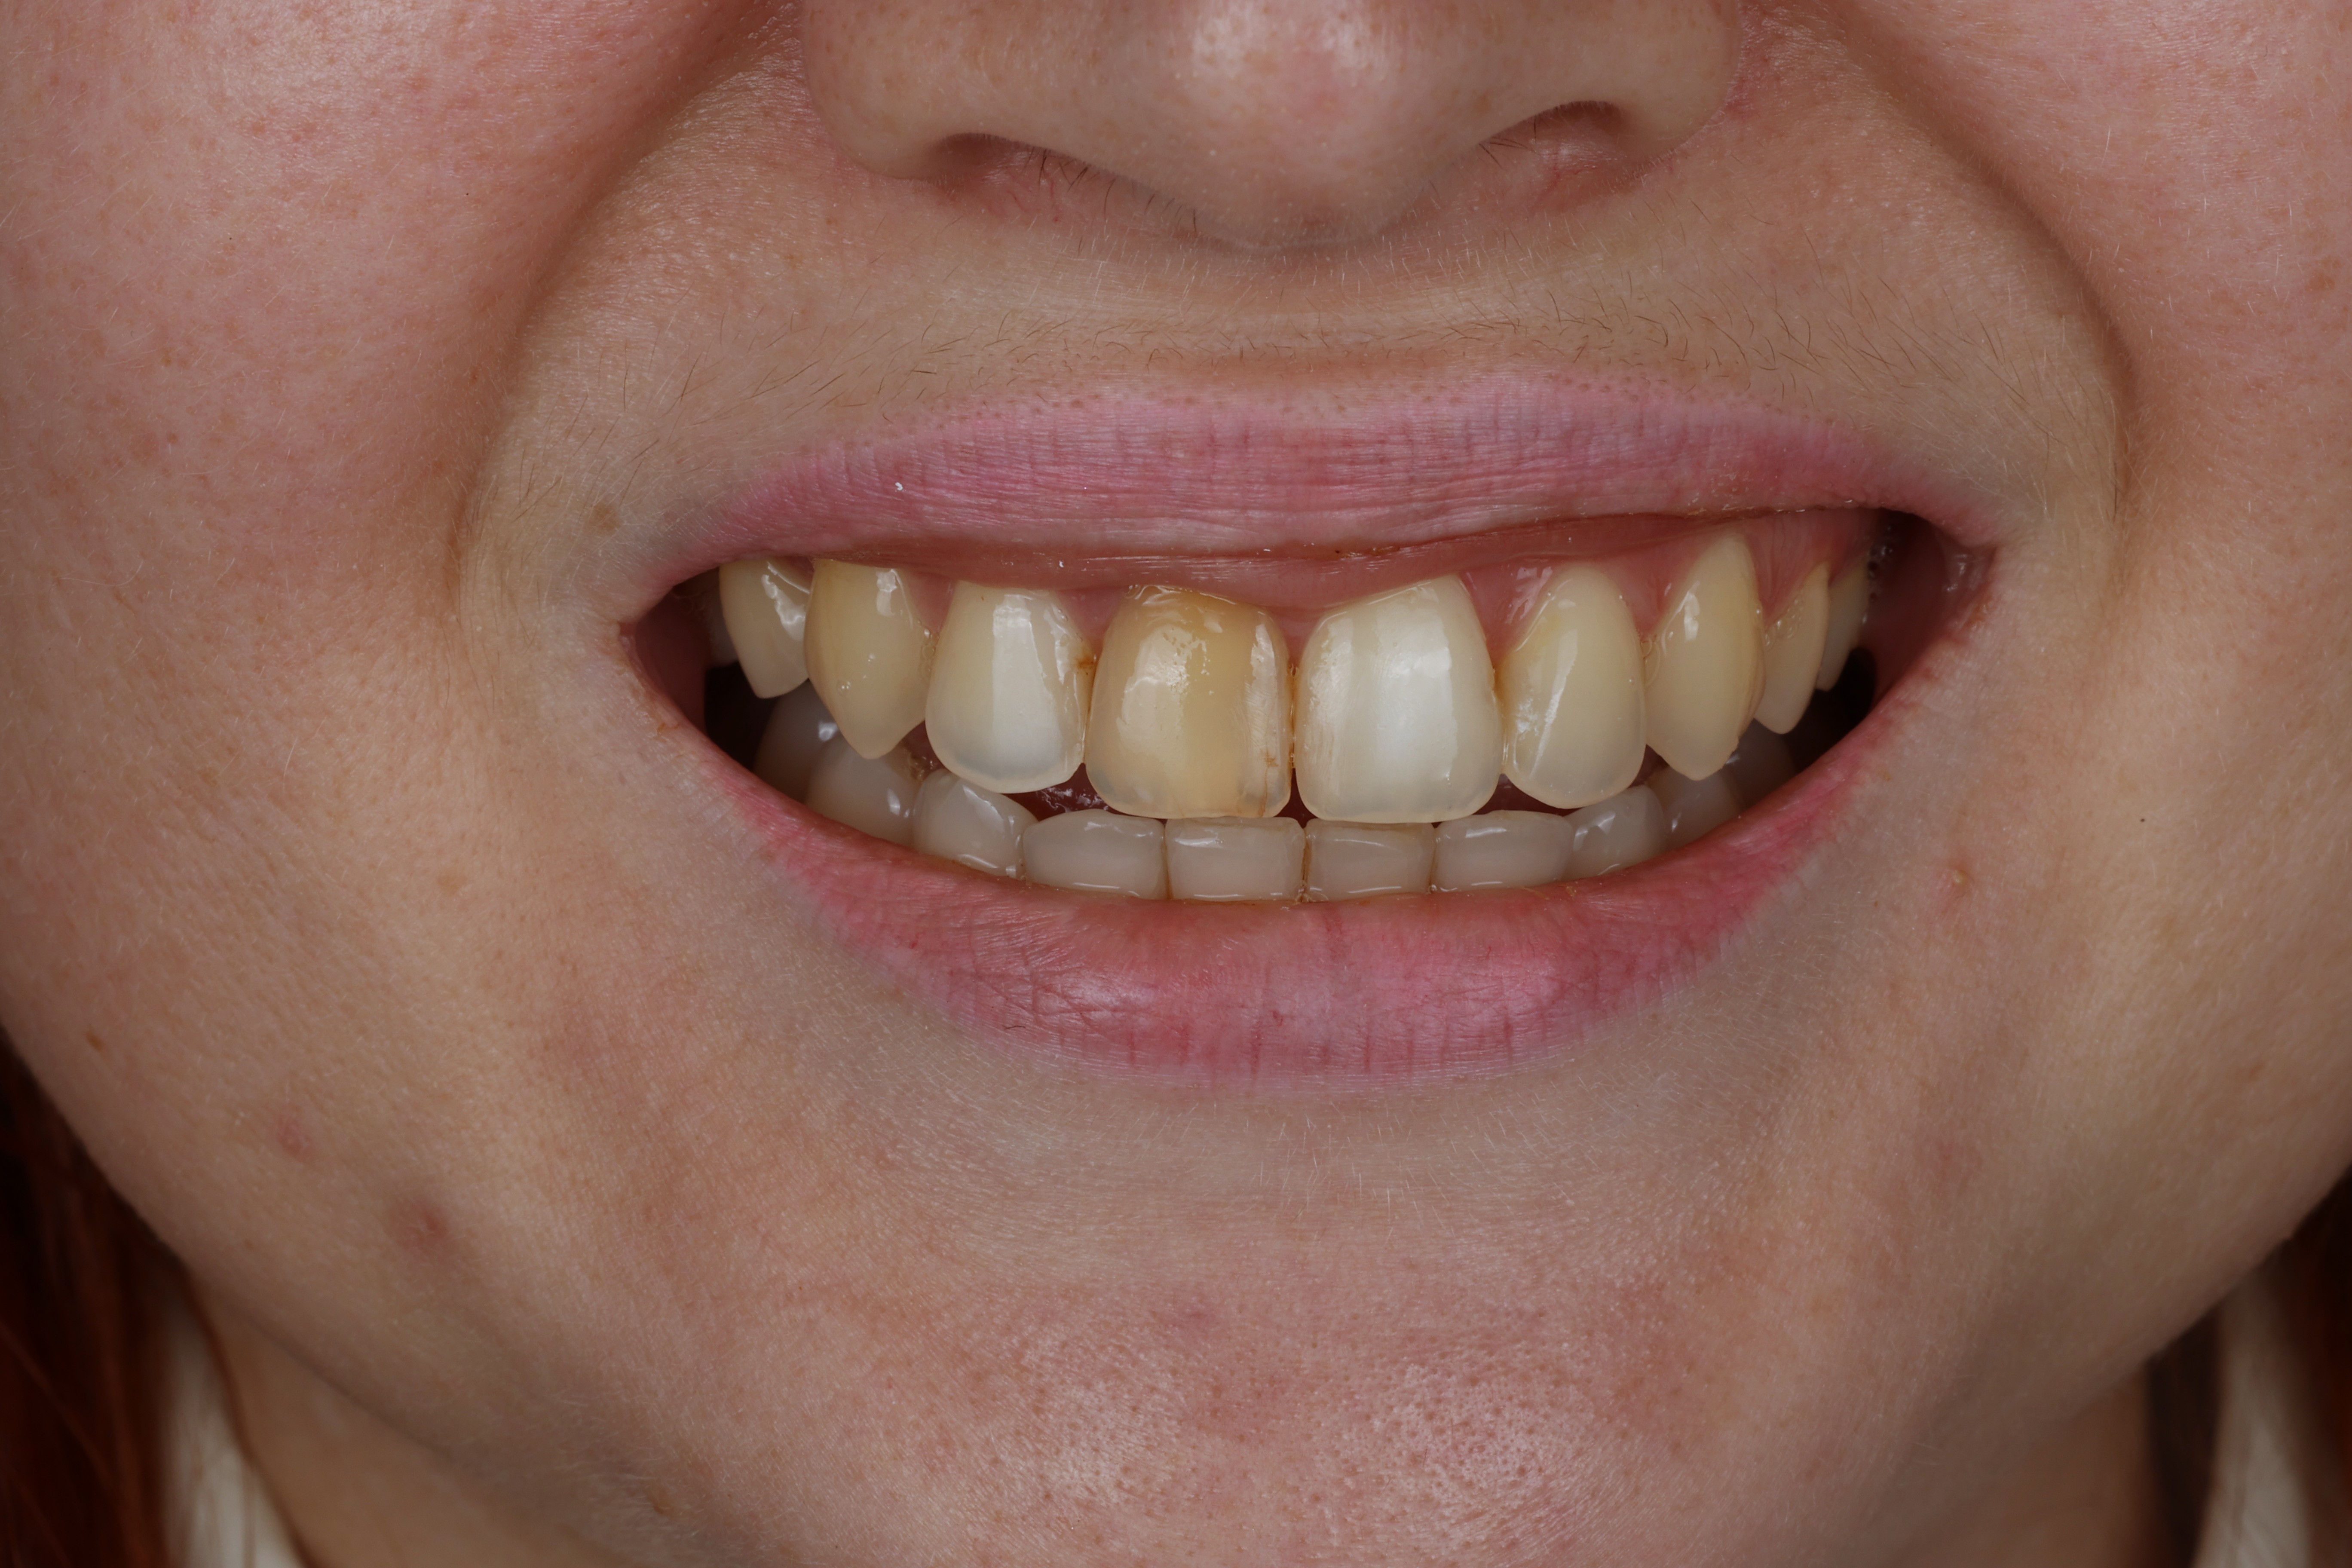

قبل

جاءت ناتاليا إلينا بعد الانتهاء من علاج تقويم الأسنان. كانت مشكلتها الرئيسية هي السن الأمامي المتغير اللون، والذي كان بارزًا ويجعلها تشعر بعدم الثقة.